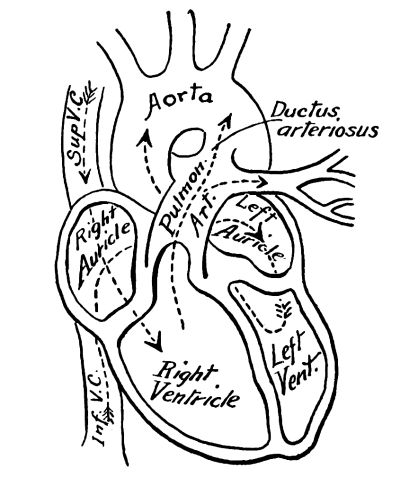

The Heart, 101—The Pericardium, 101—Cavities of the Heart, 103—The Endocardium, 103—The Valves of the Heart, 103—Circulation, 105—Circulation in the Fetus, 106—Arteries, 107—Veins, 109—Portal Circulation, 109—Pulmonary Circulation, 110—Nerves of the Heart, 110—Heart Sounds, 111—The Heart Beat, 111—Factors Affecting Circulation, 112—The Pulse, 113—Blood Pressure, 114—Nerve Supply of the Blood-vessels, 115—The Blood, 116—Composition of the Blood, 116—Coagulability of the Blood, 117—Blood-corpuscles, 118. |